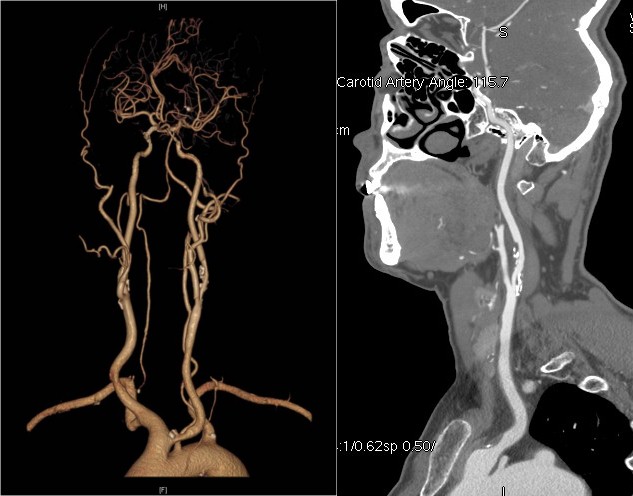

清华长庚血管外科 9月8日(通讯员 赵克强 吴巍巍)王先生今年50岁,头晕、黑矇反复发作,1周前超声发现左侧颈动脉狭窄,赶紧就诊于清华长庚医院,颈动脉CTA发现王先生的左侧颈内动脉起始端粥样硬化斑块形成、重度狭窄,病变位置很高,更复杂的是还同时合并颈总动脉起始部狭窄(图1、2)。入院后血管外科医生为王先生进行了全面的颈动脉斑块性质评估:超声造影检查发现斑块内线样增强提示斑块内新生血管;斑块MRI分析均提示斑块内出血。上述评估均提示该斑块可能为不稳定斑块,极易脱落导致脑梗死,头颅核磁也证实了左侧颈动脉供血区域大脑半球多发腔隙性梗塞。结合王先生的症状、狭窄程度以及斑块不稳定性质,进行斑块剥离手术或微创支架手术的指证明确,由于CTA提示颈动脉狭窄病变很高,剥离手术风险高,我们决定为王先生施行微创手术。

术前CTA提示王先生的主动脉弓形为“牛”型解剖变异(左侧颈总动脉从无名动脉发出,图1),颈总动脉起始部及颈内动脉均存在斑块狭窄,为手术增加了难度,经过仔细讨论分析病情,血管外科吴巍巍主任、赵克强教授决定“另辟蹊径”,从患者右上肢入路,实施微创颈动脉支架手术,同期解决颈总及颈内动脉两处病变。经过充分的术前准备,吴巍巍主任和赵克强教授在麻醉科医师的保驾下联手为王先生安全实施颈动脉微创支架植入术(图3、4),避免了王先生今后再次发生严重的脑卒中事件。术后返回病房,精准调控血压、心率,5天后王先生顺利康复出院。

图1 颈动脉狭窄病变很高合并颈总动脉狭窄合并牛型弓